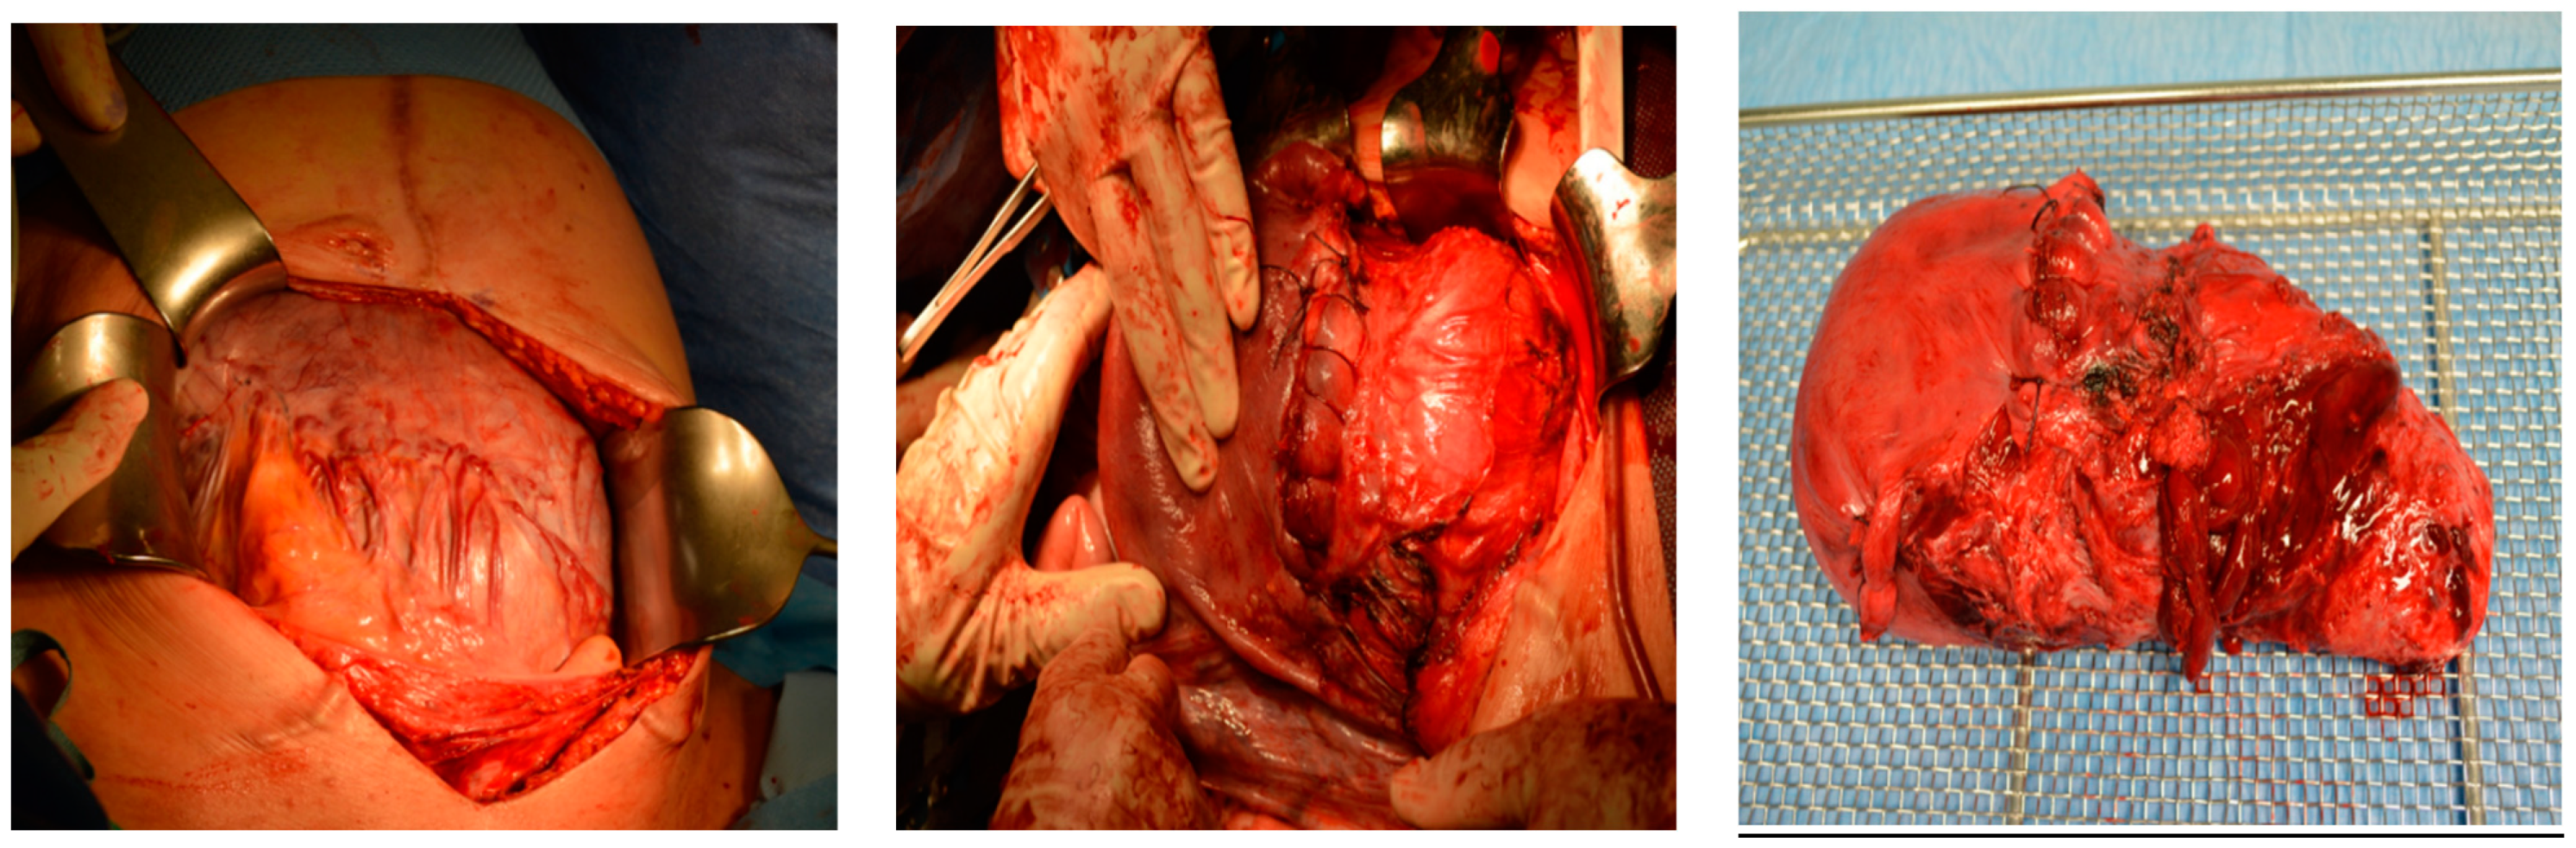

Intraoperative findings (Figure 8):

Figure 8.

Depict the uterus during and after hysterectomy performed for placenta increta.

Histological findings of the uterus weighing 939 g revealed the following:

- Parts of a placenta increta located close to the sutured ruptured area.

- Absence of decidua basalis in the affected area, with focal necroses visible.

- The rest of the serosa showed no additional pathological findings.